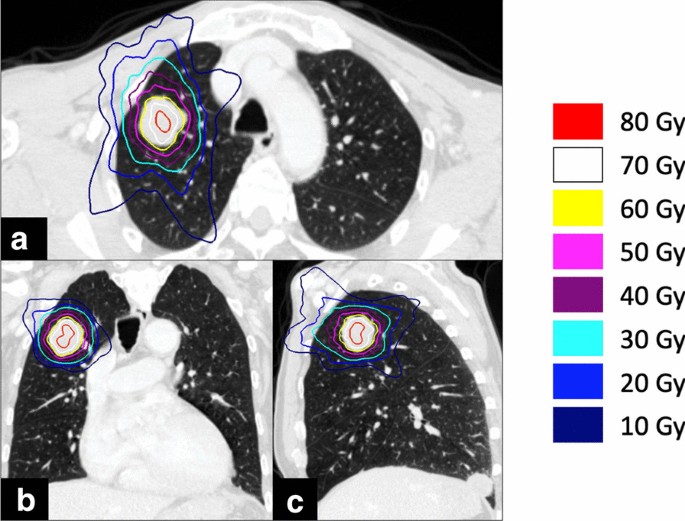

A 76-year-old Japanese man with right oropharynx ACC presented at a general hospital. Computed tomography (CT) detected masses of 23 × 19 mm on the right upper lung lobe, 14 × 12 mm on the right lower lung lobe, and 15 × 14 mm on the left lower lung lobe. 18F-fluorodeoxyglucose positron emission tomography (FDG-PET) revealed abnormal accumulation in the lung tumors. The patient was diagnosed with T3N0M1, stage IVC ACC of the right oropharynx with lung metastases. Despite the lung metastasis, a favorable long-term prognosis was possible after control of the primary tumor. Radical surgery was not indicated for reasons related to functional preservation, and the patient received carbon ion (C-ion) radiotherapy for the primary tumor. The total dose was 64 Gy (relative biological effectiveness) delivered in 16 fractions. After 30 months, there was no recurrence of the primary lesion; however, the metastatic lung tumors had increased in size. The masses had grown to 32 × 30 mm on the right upper lung lobe, 31 × 25 mm on the right lower lung lobe, and 18 × 17 mm on the left lower lung lobe (Fig. 1). The patient consented to sequential treatment with CyberKnife for multiple lung metastases (Table 1). CT images of 1 mm thickness were acquired to plan the treatment. Respiratory migration was assessed by four-dimensional CT. The gross tumor volume (GTV) was delineated based on thin-slice CT images. The clinical target volume (CTV) was identical to the GTV (CTV = GTV). The planning target volume (PTV) included 2 mm margins surrounding the CTV. The organs at risk (OARs; lung, spinal cord, heart, and skin) were outlined on the treatment planning CT scan and dose–volume histogram analysis. D95 was defined as the minimum dose covering 95% of the GTV for the first and the second CyberKnife treatments or the PTV for the third CyberKnife treatment. The dose prescribed for the PTV was used for the third treatment because of its small size. The patient received a total dose of 60 Gy in 10 fractions of D95. The treatment was planned using the MultiPlan System (Accuray). The composite dose distribution is depicted in Fig. 2. The treatment data for the first CyberKnife administration are summarized in Table 2. Conformity and homogeneity indices were calculated according to the following formulas [8]:

The conformity and homogeneity indices were 1.09 and 1.45, respectively.